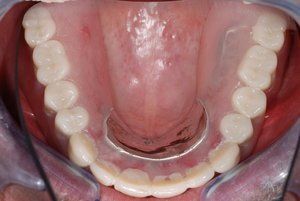

At Dental Innovations in Wasilla, AK, we can fit the very latest implant supported dentures, implant retained dentures, or more complex or targeted solutions for a particular patient situation. Contact our team today to arrange a consultation.